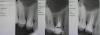

Kolchanov Опубликовано 9 февраля, 2013 Поделиться Опубликовано 9 февраля, 2013 Хочу поинтересоваться у докторов. Вот бывают случаи, когда при перелечке в апексе ну не идет. Причем абсолютно ясно, что там не ступень (лечили в то время, когда кроме пульпэкстракторов нифига не было) и, скорее всего, не материал. Как-то читал в одной умной книге, что облитерации в апексе практически не бывает, что мол мало там одонтобластов. А вот на практике не идет...Вот случаи.Последний случай.Клычара слева на снимке. Лечен при царе Горохе, никого не беспокоит кроме ортопеда. Подгнившая по краям племба и какая-то паста довольно плотная в канале. Никакой проходимости не получено, дрилить не стал.ДиагностикаС кальцием после первого посещенияОбтурированный Более ранний случай.Тоже клык только верхний. Условия примерно те же. После мы его с ортопедом удалили, из-за амфодонтоза Нижнее правое фото - состояние на момент удаления. До сих пор лежит дома, ждет случая быть распиленным. Нужен микроскоп какой-нибудь... И третий случай.Паренек с пломбой из композита. Когда-то лечился, в каналах обнаружилось что-то типа йодоформно-гидроксидное. Опять никакого беспокойства, просто ревизия. Удалось то, что удалось. Собственно вопросы:1) Как долго ковыряете в таких случаях?2) Как долго моете, когда стало ясно, что дальше не проковырять?3) Что дальше? Ждете или сразу реставрация? Я имею ввиду случая асимптоматики, в т.ч. и рентгенологической. Ссылка на комментарий

Kolchanov Опубликовано 10 февраля, 2013 Автор Поделиться Опубликовано 10 февраля, 2013 Нет, тут не за резорцинки речь. Тут в двух случаях были пасты и в одном что-то гидроксидное.Инструменты. Стальные мани от 8 до 80, протейперы есть, профайлы 25, 30 и 35 04 и 06 конусностей, патфайлы где-то валяются.А что ЭДТА там в канале сильно помогает? Что-то мне думается, что оно там на мизерную толщину разрыхлит и инактивируется. Я его вообще перестал год назад при обработке использовать. Только в конце иногда. Может с оптикой например в премоляре и можно было бы поглубже ультразвуком каким-нибудь подолбить, но я со своими глубже 2-3мм от устья не вижу, та и то надо раздолбить. Меня собственно интересовал предел терпения Вот я ковыряю первое посещение где-то 30 мин. Больше времени просто нет. Второе посещение - около 1.5 часов плюс минус. Если через полчаса подгибаний, кручения и верчения файлов я понимаю, что не идет. Я на все плюю, где-то минут 10 мою с активацией гуттаперчевой и забиваю как оно есть.Иногда получается вот такНо чаще фигу там. Просто короткая полоска. 2 Ссылка на комментарий

ger_berra Опубликовано 10 февраля, 2013 Поделиться Опубликовано 10 февраля, 2013 Иногда получается вот так Тут хорошо запаковано. Ссылка на комментарий